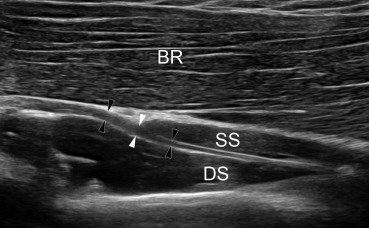

- 가이온 터널/ 기용터널 (Guyon's canal)은 손목 부위에서 척골신경(Ulnar nerve)이 지나가는 아주...